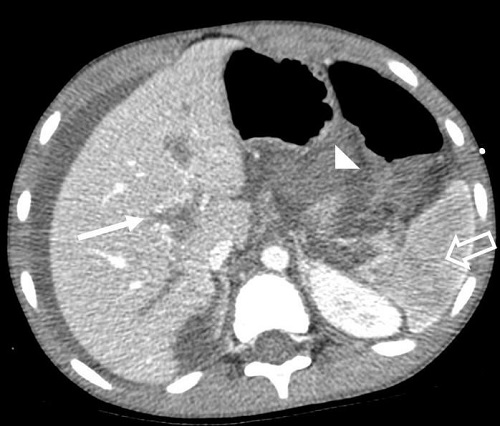

Se presenta el caso de un niño de 8 años sin antecedentes personales que acude a Urgencias con dolor abdominal de 48 horas de evolución, acompañado de vómitos y hematoquecia, siendo la analítica anodina. Tres horas después, el paciente presenta pérdida de conciencia junto a palidez intensa. Ante el cuadro clínico con persistencia del dolor abdominal, se solicitó ecografía abdominal, donde se visualizó engrosamiento de pared de las asas intestinales, ausencia de peristaltismo, hiperecogenicidad de la grasa y abundante ascitis (Fig. 1). Se identificaron arteria hepática, vena cava inferior y venas suprahepáticas permeables, no observando flujo en la vena porta, en el hilio hepático ni en las ramas intrahepáticas. Por ello, se decidió completar el estudio con tomografía computarizada (TC) con contraste intravenoso en fases arterial, portal y tardía, confirmando trombosis de vena porta con extensión a eje esplenomesentérico, infarto esplénico y ausencia de realce de asas intestinales en relación con proceso isquémico (Fig. 2).

| Figura 1. Imagen de ecografía abdominal donde se visualizan asas intestinales (flechas) con importante engrosamiento parietal, de hasta 6,6 mm. |